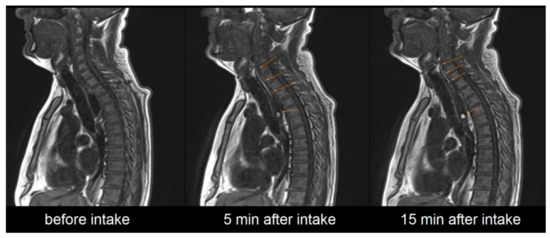

It needs to be highlighted that after successful application the contrasting film could be detected on MRI in all cases. In 25 out of 36 administrations the contrast-enhanced polymer film was still detectable in the esophagus, even 15 min after administration of the EsoCap system, as shown in Figure 4.

Figure 4.

Exemplary representation of sagittal image acquisition before, 5 min after and 15 min after intake of the EsoCap system.